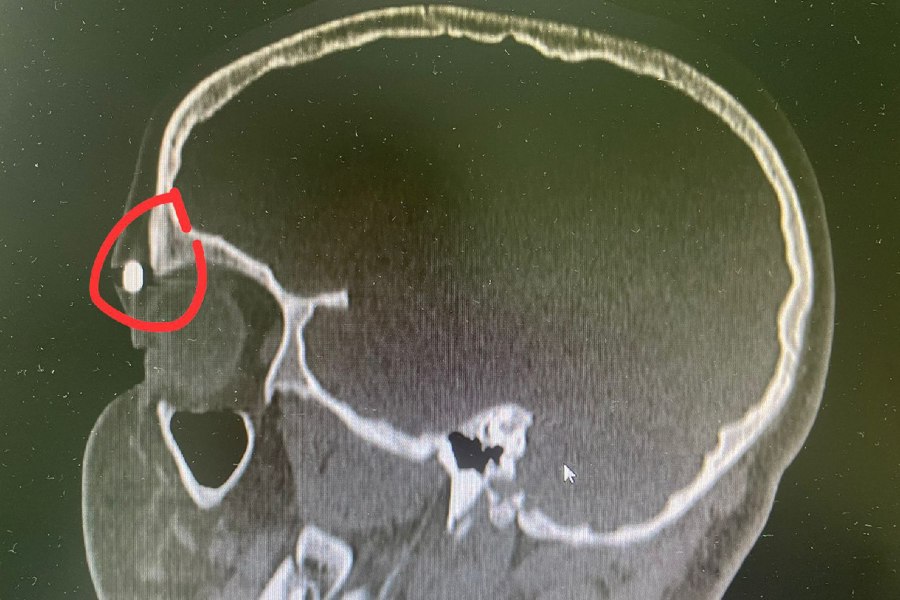

Врачи оказали помощь 10-летнему мальчику, который получил ранение из пневматического оружия. Со слов пациента, он был один дома, когда нашел отцовский пистолет. Вместе с друзьями решили хорошо провести время и пострелять по банкам, к сожалению, игра закончилась неудачно, так как пуля отрикошетила мальчику в прямо лоб.

Была проведена операция. К счастью все закончилось хорошо.